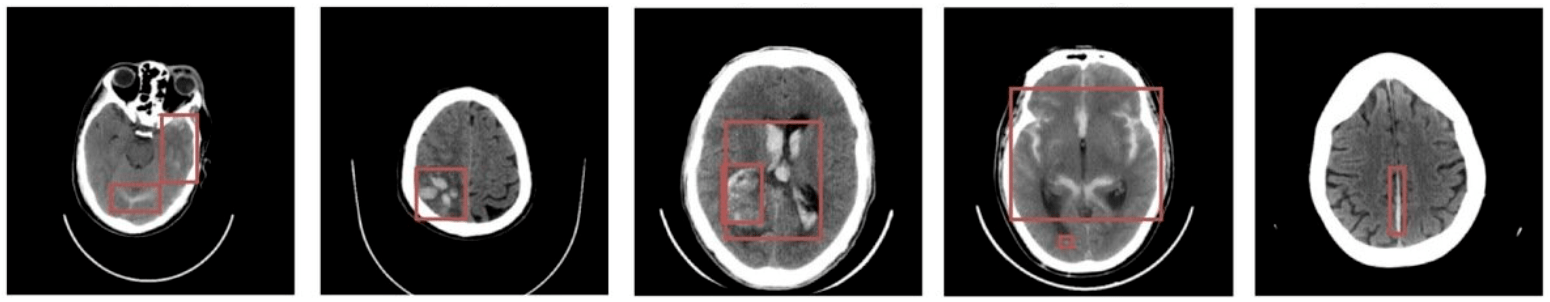

Question 4:

What can we do with them?

Hemorrhage detection in head CT

Image-by-image supervision (strong learner)

one label per image!

Study/volume supervision (weak learner)

one label per study!

• Weak learner is more efficient for detecting positive slices

• Can find hemorrhages without labels

Teneggi, J., Yi, P. H., & Sulam, J. (2023). Examination-level supervision for deep learning–based intracranial hemorrhage detection at head CT. Radiology: Artificial Intelligence